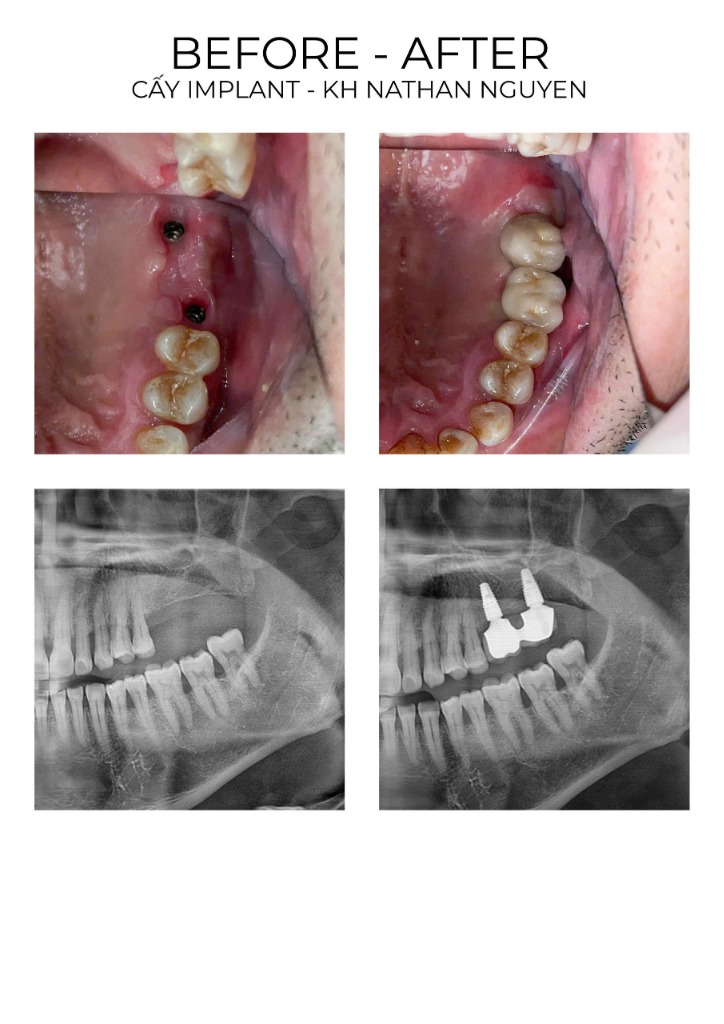

BẰNG CHỨNG THUYẾT PHỤC NHẤT

Hãy xem cộng đồng nói gì sau khi sử dụng dịch vụ Implant

Ca Implant 1

Ca Implant 2

Ca Implant 3

Ca Implant 4